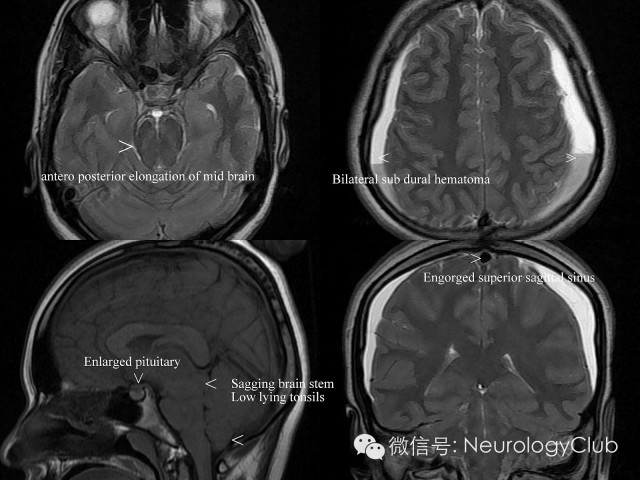

根据Monro-Kellie假说,颅内腔容积恒定不能扩张,颅内容物的总量之和即脑组织、脑血流量及脑脊液量的总和应保持恒定不变。如果其中一种成份增加必然导致另外两种成份的减少;反之,当颅内低压综合征患者的脑脊液容量减少时,必然导致另外两种成份增加。由于脑组织容积相对恒定,所以只能依靠脑血流量的变化起到代偿作用。因为软脑膜及脑实质血管有血脑屏障而硬脑膜没有,所以这种静脉的充血扩张只能表现在硬脑膜和脑静脉窦上。影像学则相应地表现为硬脑膜、硬脊膜弥漫性增厚、增强以及颅内静脉窦的扩张,垂体硬膜充血则表现为垂体增大。如果脑静脉充血扩张仍不能完全代偿,还可进一步表现为硬膜下积液。另外,在正常情况下,脑组织是漂浮在脑脊液中的,在脑脊液容量减少时,脑脊液对脑组织的浮力作用下降使脑组织向下移位,称为下垂脑,构成了影像学上的另外一组表现。

(3)静脉结构充盈(Engorgement of venous structures)

(4)垂体充血(Pituitary hyperemia)

(5)脑组织下沉(Sagging of the brain)